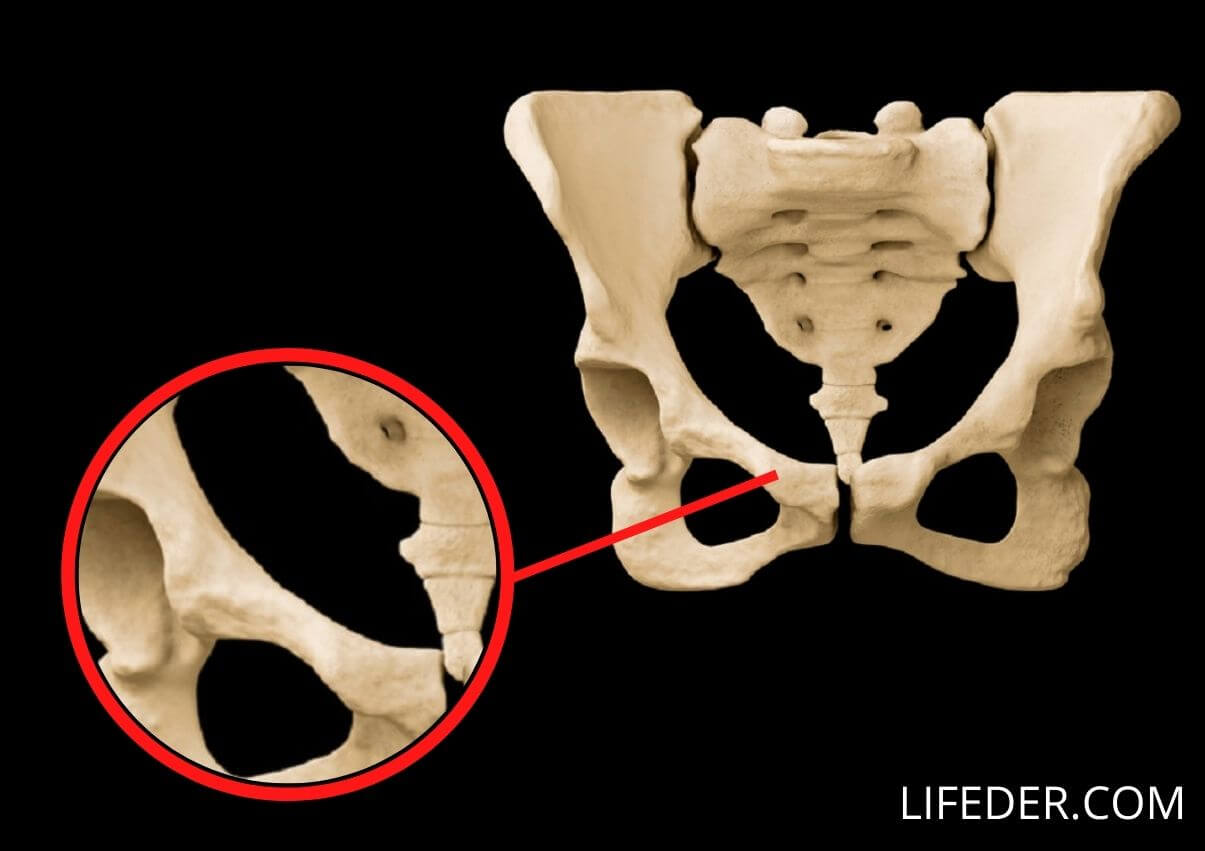

Los huesos de la pelvis

Los huesos de la pelvis incluyen el hueso ilion, el hueso isquion y el pubis. Estos huesos se organizan en dos cavidades: la pelvis mayor y la pelvis menor.

2- El isquion

El isquion se encuentra en la parte lateral de la estructura pélvica. Esta presenta una zona en la que se fijan los músculos superiores que rodean al fémur.

3- El pubis

El pubis se encuentra en parte frontal de la estructura pélvica y cierra esta estructura por el frente.